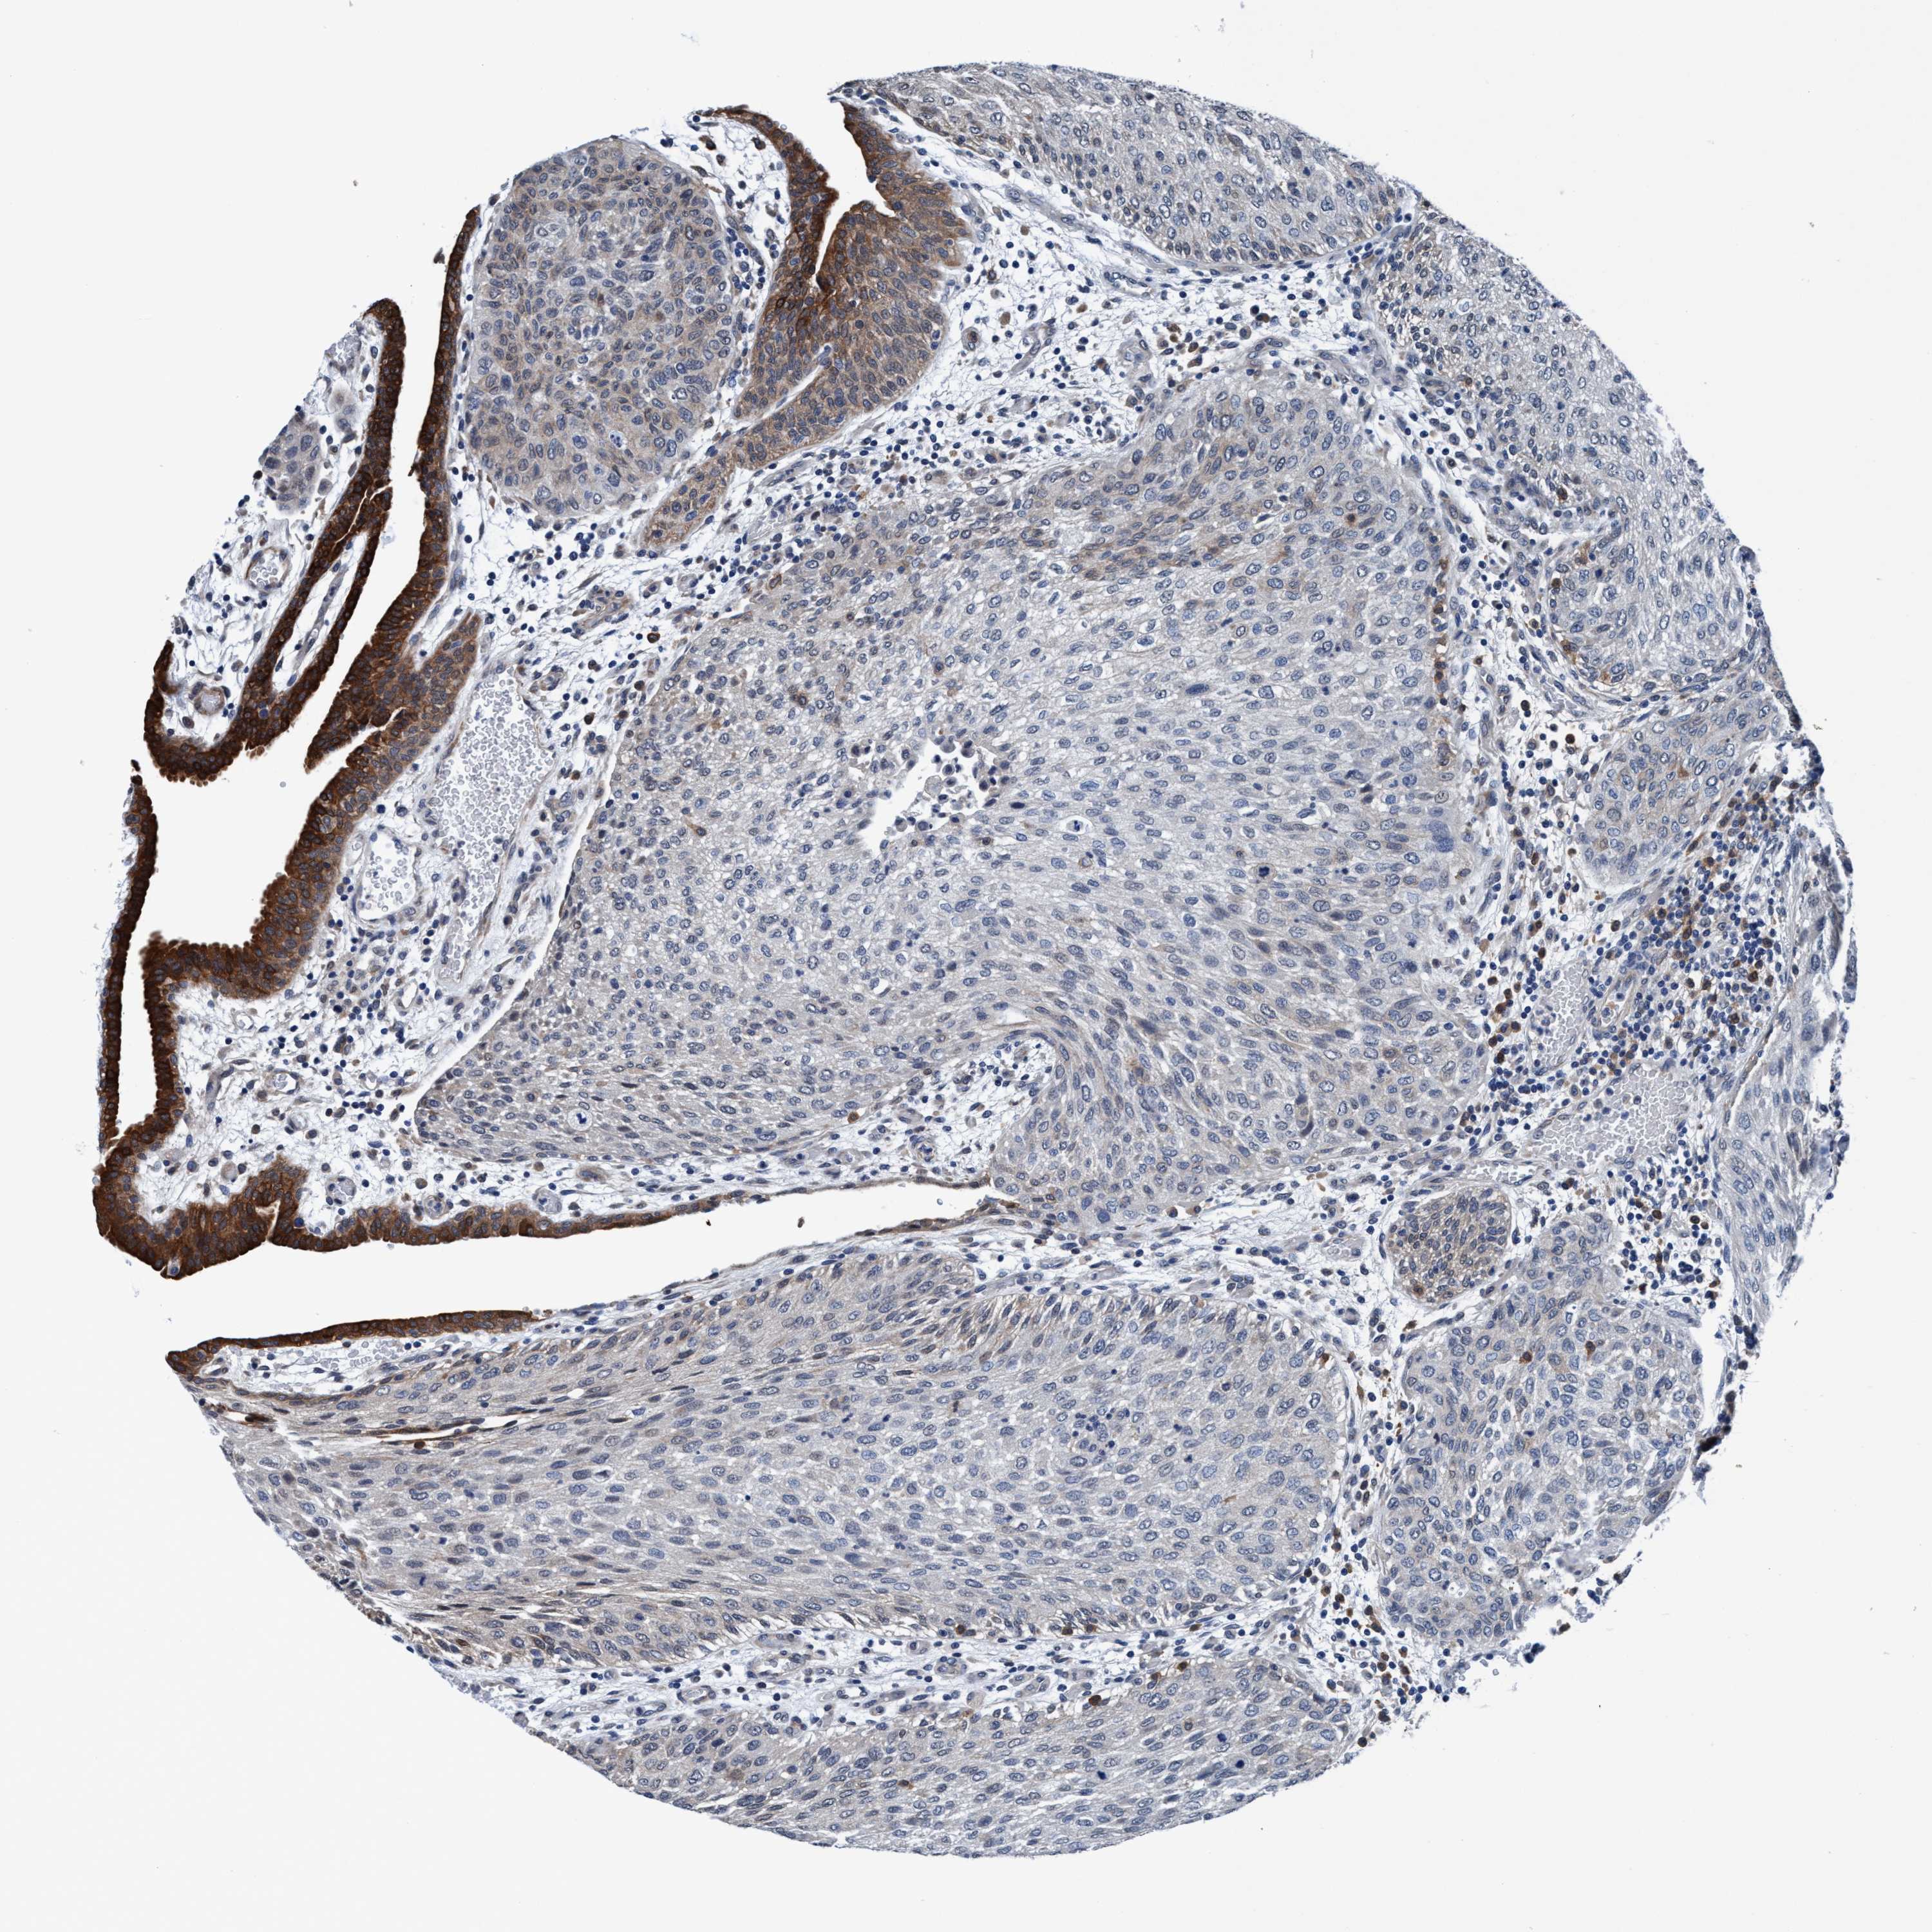

UROTHELIAL CANCER - Protein expressioni

A mouse-over function shows sample information and annotation data. Click on an image to view it in a full screen mode. Samples can be filtered based on level of antibody staining by selecting one or several of the following categories: high, medium, low and not detected. The assay and annotation is described here.

Note that samples used for immunohistochemistry by the Human Protein Atlas do not correspond to samples in the TCGA dataset.

Antibody stainingi

Antibody staining in the annotated cell types in the current human tissue is reported as not detected, low, medium, or high, based on conventional immunohistochemistry profiling in selected tissues. This score is based on the combination of the staining intensity and fraction of stained cells.

Each image is clickable and will lead to virtual microscopy that enables deeper exploration of all samples and also displays staining intensity scores, fraction scores and subcellular localization as well as patient and tissue information for each sample.

Antibody HPA008423

Urothelial carcinoma, Low grade

Urothelial carcinoma, High grade